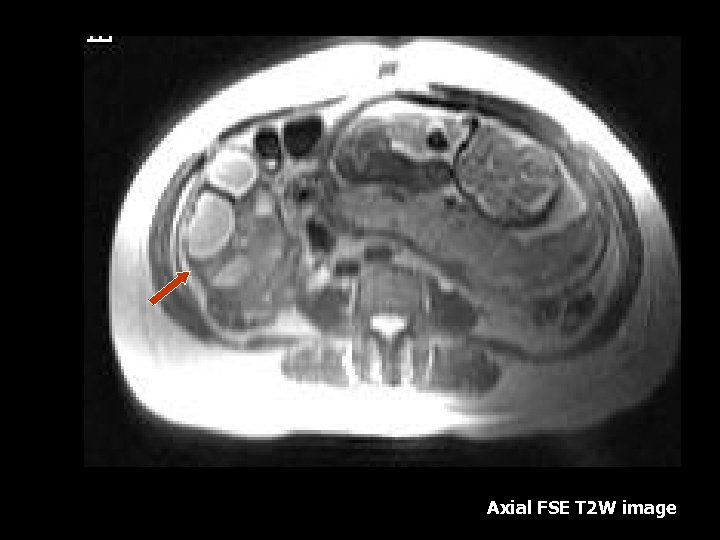

Axial SSFSE T 2 W image

Axial T 2 W image

DVT • Ovarian and Pelvic vein thromboses are uncommon complication of preganancy(7). • MRI – Acutely thrombosed vessels are enlarged and contain low signal intensity thrombus(7). • Septic thrombus can cause streaky low intensity fat stranding on T 1 W images(7).